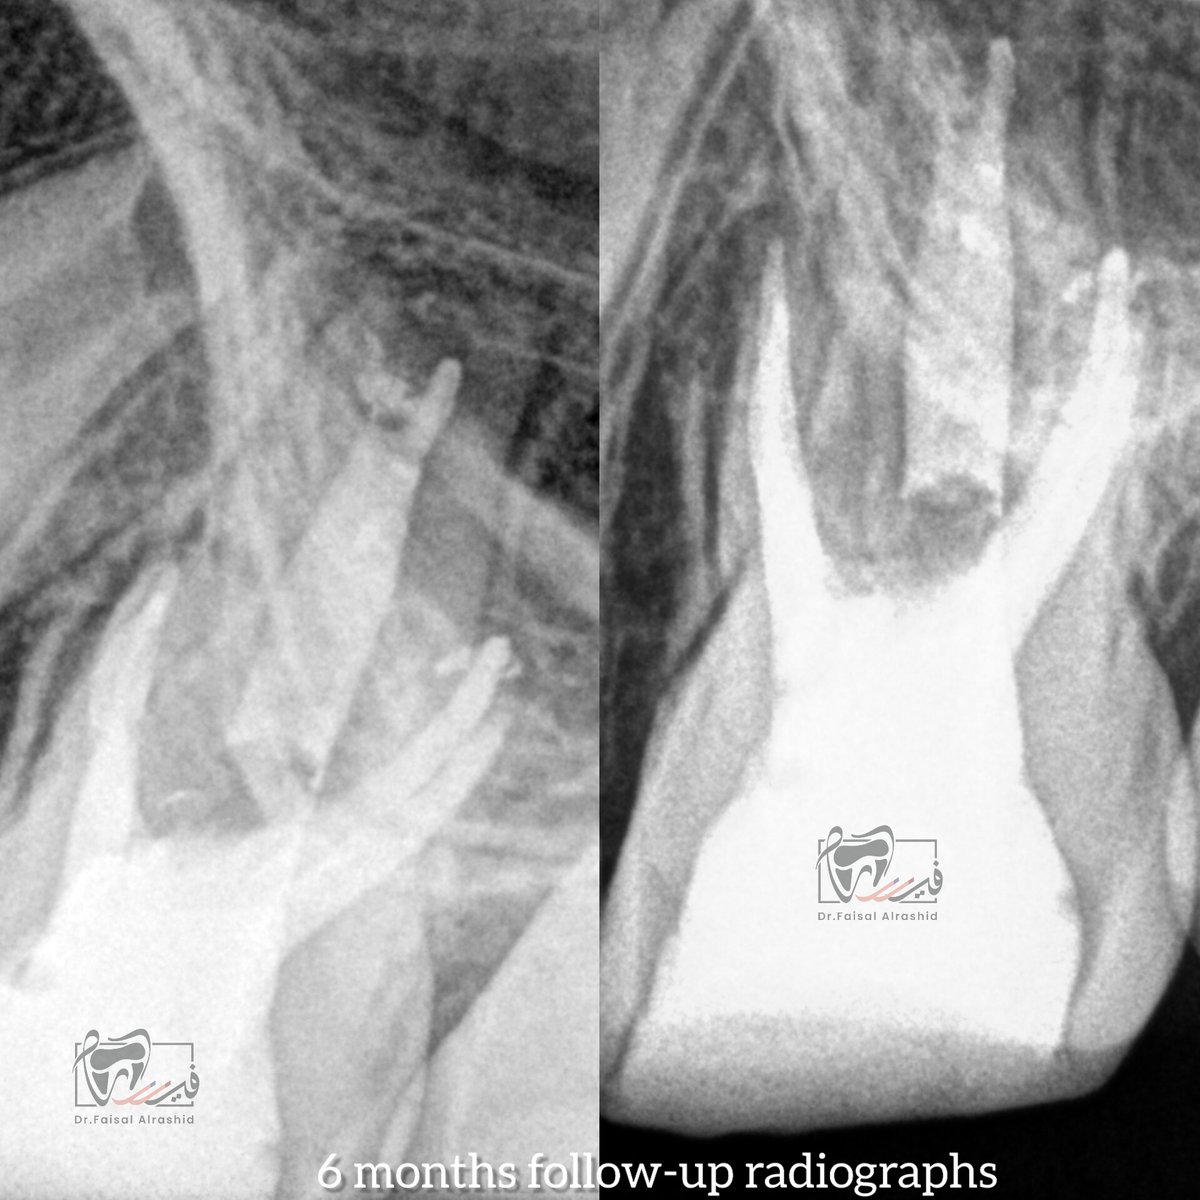

علاج عصب لضرس علوي لطفل تم علاج ٦ قنوات عصبية ولله الفضل وتمت متابعة الحاله لمدة ٦ أشهر و أبشركم بأنه بأتم صحة و عافية MB1, MB2, DB1, DB2, and P with a separate portal of exit. Regarding the P root, what exact condition does it have? *Sorry about the absence of the other PAs.

علاج عصب لضرس علوي لطفل

تم علاج ٦ قنوات عصبية ولله الفضل وتمت متابعة الحاله لمدة ٦ أشهر و أبشركم بأنه بأتم صحة و عافية

MB1, MB2, DB1, DB2, and P with a separate portal of exit.

Regarding the P root, what exact condition does it have?

*Sorry about the absence of the other PAs.